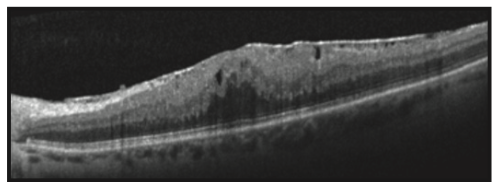

• Tomografia de Coerência Óptica (OCT): Um exame de imagem não invasivo que cria uma seção transversal detalhada da retina, permitindo visualizar a membrana e avaliar sua espessura e impacto na mácula.